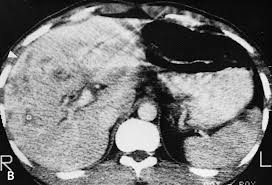

-Chụp CT scanner gan mật cho thấy có một số tổn thương giảm âm, hình bờ không đều (irregularly shaped low-attenuating lesions) có kích thước 1-4 cm;